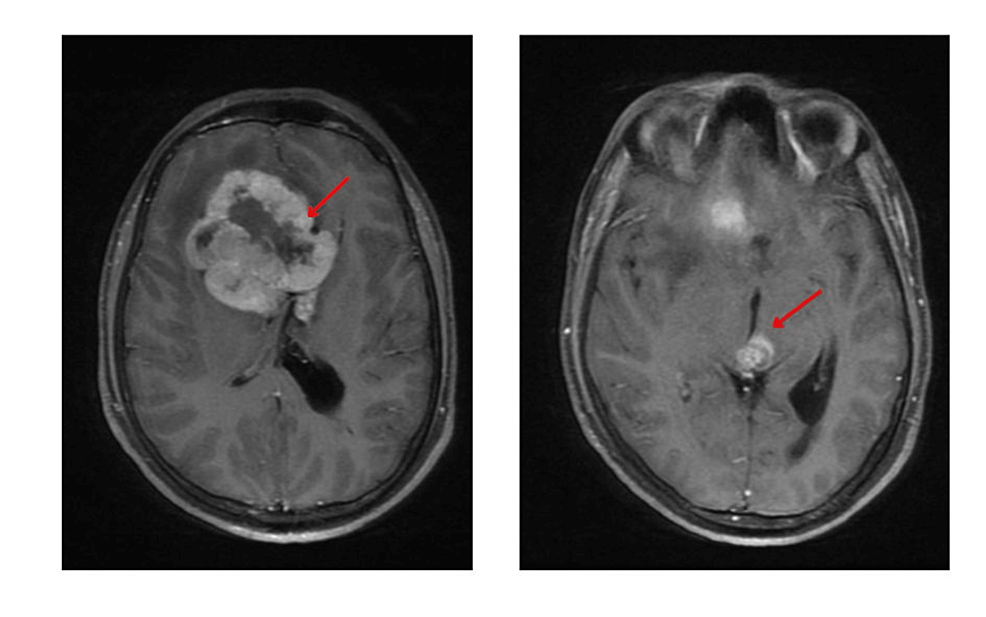

Surgery for Germ Cell Tumors in the Brain Weill Cornell Brain and

From weillcornellbrainandspine.org

Surgery for Germ Cell Tumors in the Brain Weill Cornell Brain and What's A Germ Cell Tumor Roughly 20% are cancerous, and the remainders are noncancerous. Germ cell tumours most often develop in the ovary or testicle because this is where most germ cells are. Germ cell tumors are growths of cells that form from reproductive cells. If you just found out that you or your child has a germ cell tumor, you may have a lot. What's A Germ Cell Tumor.

From www.cureus.com

Cureus A Case of NonGerminomatous Germ Cell Tumors of the Frontal What's A Germ Cell Tumor Germ cell tumors are benign (noncancerous) or malignant (cancerous) growths that arise from specialized cells called germ cells, which develop in a baby before birth (a fetus). Roughly 20% are cancerous, and the remainders are noncancerous. If you just found out that you or your child has a germ cell tumor, you may have a lot of questions about what. What's A Germ Cell Tumor.